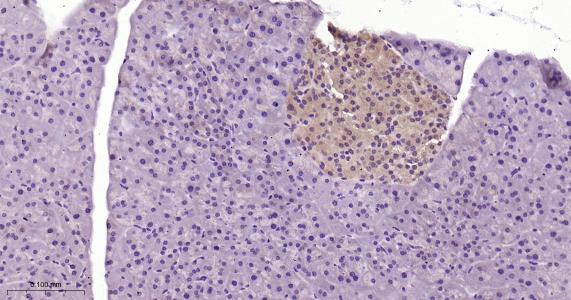

Paraformaldehyde-fixed, paraffin embedded Rat Pancreas; Antigen retrieval by boiling in sodium citrate buffer (pH6.0) for 15 min; Antibody incubation with TXNRD1 Monoclonal Antibody, Unconjugated(bsm-61558R) at 1:200 overnight at 4°C, followed by conjugation to the bs-0295G-HRP and DAB (C-0010) staining.

Paraformaldehyde-fixed, paraffin embedded Mouse Pancreas; Antigen retrieval by boiling in sodium citrate buffer (pH6.0) for 15 min; Antibody incubation with TXNRD1 Monoclonal Antibody, Unconjugated(bsm-61558R) at 1:200 overnight at 4°C, followed by conjugation to the bs-0295G-HRP and DAB (C-0010) staining.